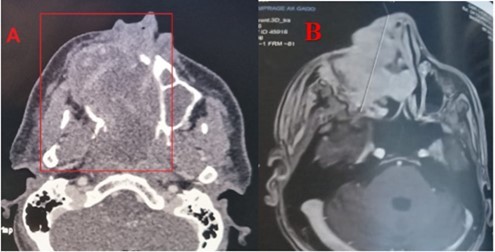

Patient aged 40 years without any surgical medical history who consults at our level in 2022 for a right epistaxis of average abundance with nasal obstruction and an induration next to the maxillary sinus right to palpation. Endoscopy revealed a reddish polypoid mass filling the right nasal cavity without palpable cervical adenopathies, CT returned in favor of an expansive tissue process of the right maxillary sinus, extended to the soft parts and the homolateral nasal cavity. The complete resection of the mass was performed by endonasal surgery (endoscopic maxilectomy). The histological examination found hemangioendothelioma without signs of malignancy with infiltrated margins, external complementary radiotherapy was indicated (50 Gy, 2Gy per day for 5 days a week on the maxillary sinus), a radiological check (MRI) 4 months later does not find any residual tumor. After an absence of 15 months, the patient revisits for resumption of symptomatology with right epistaxis of great abundance requiring 2 globular units, a reddish mass protruding from the nasal vestibule, lysing the bony palate with extension towards the cheek (Figure 1) and alteration of the CT and MRI find an expansive tumor process centered on the nasal cavity and maxillary sinus right of 103x 58 x41 vs 156x67x95mm with currently highly elevated spans, the process is globally hypodense and weakly elevated, presence of some vessels as well as hypervascular portions of peripheral localization at the extended jugal level and in front of the internal canthus, bone palace lysis, with a negative extension balance (Figure 2).

Figure 2.CT scan with PC injection (A) and MRI in axial sections (B) showing the lesion of the right maxillary sinus extended to neighboring structures

Angiosarcoma is a very rare malignant tumour that accounts for about 1 to 2% of all sarcomas 1. Nasosinusial localization is exceptional: 4% of angiosarcomas occur in the pharynx, oral cavity or sinuses 8; only 24 cases have been reported from 1974 to 2009 9. The age range varied between 8 and 81 years, our patient was 40 years old, with a male predominance (16 men for 8women in the 24 cases reported), which was the case with our patient 10. The etiopathogenesis of angiosarcomas is not known, radiation exposure presents a risk up to seven times greater for secondary angiosarcoma 9, vinyl chloride, arsenic and thorium dioxide, which could cause lymphedema, would cause angiosarcoma 11 in our patient, where there was secondary sarcomatous transformation after irradiation. The clinical presentation of angiosarcoma is generally mild in the initial phase 6. The macroscopic aspect is unspecific 12. It comes in the form of polyps or red or purplish plaques sometimes taking the appearance of a hematoma. This misleading clinical aspect requires follow-up and biopsy at the slightest doubt. Our patient had unilateral nasal obstruction with epistaxis of small abundances and smooth reddish mass in the nasal cavity and, at a later stage, the tumor syndrome becomes evident (epistaxis of great abundance, blocked nose, alteration of the general condition) with extension to surrounding structures (eyeball, palate, skin). The radiological presentation is extremely variable and not very specific. On imaging, the tumour has variable dimensions (ranging from 2 to 8 cm in published cases) with hypervascular lesion, heterogeneous contrast uptake and signs of bone lysis on CT scan, and can be evaluated for its extent. In MRI, the tumour has a low-intensity signal on T1 weighted sequences and a high-intensity heterogeneous signal on T2-weighted sequences with an enhancement of intense and heterogeneous contrast 4. The diagnosis of certainty is established by histopathological staining and confirmed by immunohistochemistry 1, 3. Three microscopic aspects have been described: fusiform cells of the epithelioid type and of the undifferentiated or solid type. In undifferentiated forms, the vascular marker CD31 is useful for diagnosis. Other less specific or sensitive markers may be used (Willebrand factor, CD34, lectins) 9. Epithelioid forms pose the problem of differential diagnosis with poorly differentiated squamous cell carcinomas, especially since there is a strong expression of AE1/AE3 cytokeratins in angiosarcoma. In the present case, fusiform cells with CD31 positive vascular markers were found to support the diagnosis of fusiform angiosarcoma NOS 13. Differential diagnosis includes hemangioma, intravascular papillary endothelial hyperplasia (Masson disease), juvenile nasopharyngeal angiofibroma, hemangiopericytoma, Kaposi sarcoma and malignant melanoma 14. The prognosis of these tumours remains bleak today. At five years, there are between 30 and 45% survivors in the localized stage 15. The main prognostic factors are a pejorative size greater than five centimeters; in our patient, the mass has reached 10 cm, a high histological grade, an age greater than 70 years. Resectability, non-RO surgery, and absence of multimodal treatment 16. The treatment is based on surgery (adapted to tumor location and extension) followed by radiation therapy. Other treatment modalities have been tried, such as chemotherapy, radiosurgery (gamma knife) 11, and interleukins 17; and trials with propranolol are currently underway 18. However, no standardized therapeutic management has been defined given the limited number of published cases and the absence of comparative studies. Five-year survival is 22% (versus 12% for soft tissue angiosarcoma in the head and neck) and depends on the degree of tumor differentiation and stage at diagnosis 19. Distant metastases may occur in 30% of cases within the first 24 months; metastases involve bones, lungs, liver, skin or cervix 10.